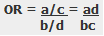

For statistical results, case-control studies typically produce an odds ratio for each potential risk factor. The equation below shows how to calculate an odds ratio for a case-control study.

Notice how this ratio takes the exposure odds in the case group and divides it by the exposure odds in the control group. Consequently, it quantifies how much higher the odds of exposure are among cases than the controls.

In general, odds ratios greater than one flag potential risk factors because they indicate that exposure was higher in the case group than in the control group. Furthermore, higher ratios signify stronger associations between exposure and the medical condition.

An odds ratio of one indicates that exposure was the same in the case and control groups. Nothing to see here!

Ratios less than one might identify protective factors.

The odds ratio (OR) is used in case-control studies to estimate the strength of the association between exposure and outcome. Note that it is not possible to estimate the incidence of disease from a case control study unless the study is population based and all cases in a defined population are obtained.

The results of a case-control study can be presented in a 2x2 table as follow:

The odds ratio is a measure of the odds of disease in the exposed compared to the odds of disease in the unexposed (controls) and is calculated as:

Example: Calculation of the OR from a hypothetical case-control study of smoking and cancer of the pancreas among 100 cases and 400 controls. Table 1. Hypothetical case-control study of smoking and cancer of the pancreas.

OR = 60 x 300 100 x 40 OR = 4.5 The OR calculated from the hypothetical data in table 1 estimates that smokers are 4.5 times more likely to develop cancer of the pancreas than non-smokers. NB: The odds ratio of smoking and cancer of the pancreas has been performed without adjusting for potential confounders. Further analysis of the data would involve stratifying by levels of potential confounders such as age. The 2x2 table can then be extended to allow for stratum specific rates of the confounding variable(s) to be calculated and, where appropriate, an overall summary measure, adjusted for the effects of confounding, and a statistical test of significance can also be calculated. In addition, confidence intervals for the odds ratio would also be presented.